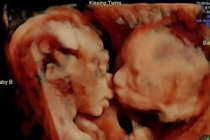

| Ảnh siêu âm được lan truyền rộng khắp của Sharni. |

| Bà bầu cho biết mình sẽ không phá thai và đây là ảnh "sọ người bình thường". |